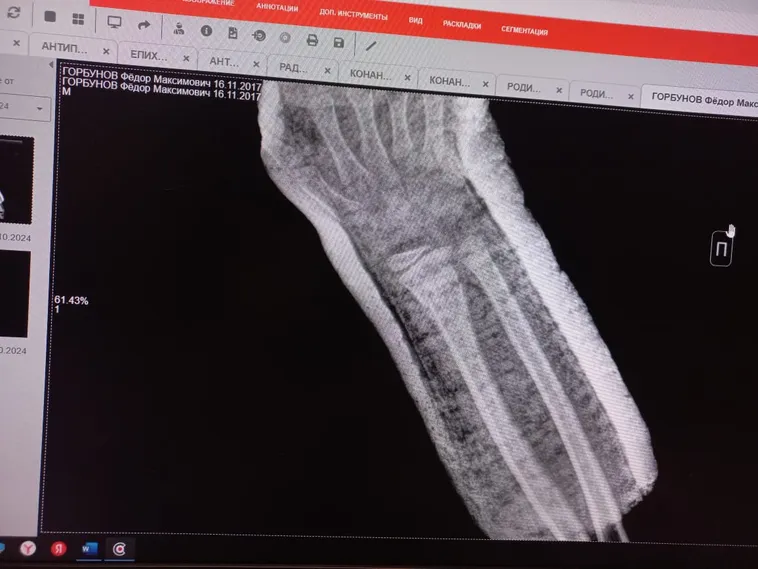

Пример 1: ребёнок, 8 лет, случай максимальной точности консолидации. Перелом двух костей предплечья. Две недели применения методики - акустический контактный резонансный метод Healingbowl® дополнительно к основной терапии. Применялась коллекционная поющая чаша Healingbowl® Luxury Mustang®, частота около 130 Гц. Это было пробное лечение под руководством Виктора Петровича, всё согласовано с родителями.

Применение чаши по методике доктора Сурикова позволило ускорить регенерацию в какой-то степени, регенерация шла на очень высоком уровне. Получен дополнительный седативный эффект, ребёнок быстро засыпал, чаши не боялся. Вибрация обезболила, убрала отек, улучшила дренажную функцию, способствовала сокращению сроков регенерации тканей.